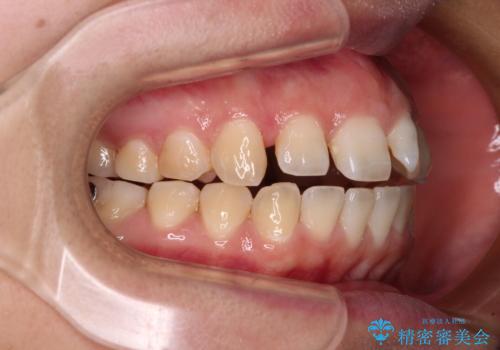

- 上下の前歯が非接触であることと、それに伴う口元の閉じにくさを気にして来院された患者様です。

奥歯の咬み合わせを見ると、上顎が下顎に対して相対的に前方にありました。

口元の閉じにくさを改善するためには、上顎臼歯を後方に移動させた咬み合わせにする必要があります。

インビザライン単体で改善することも可能ですが、達成する可能性が高くないため、カリエールディスタライザーという補助装置を併用して、より確実性を上げることとしました。

奥歯の咬み合わせを改善しながら、並行してインビザラインで歯列を整えることとしました。

カリエールディスタライザーを併用したことで、確実かつ短期間で治療を終えることができました。